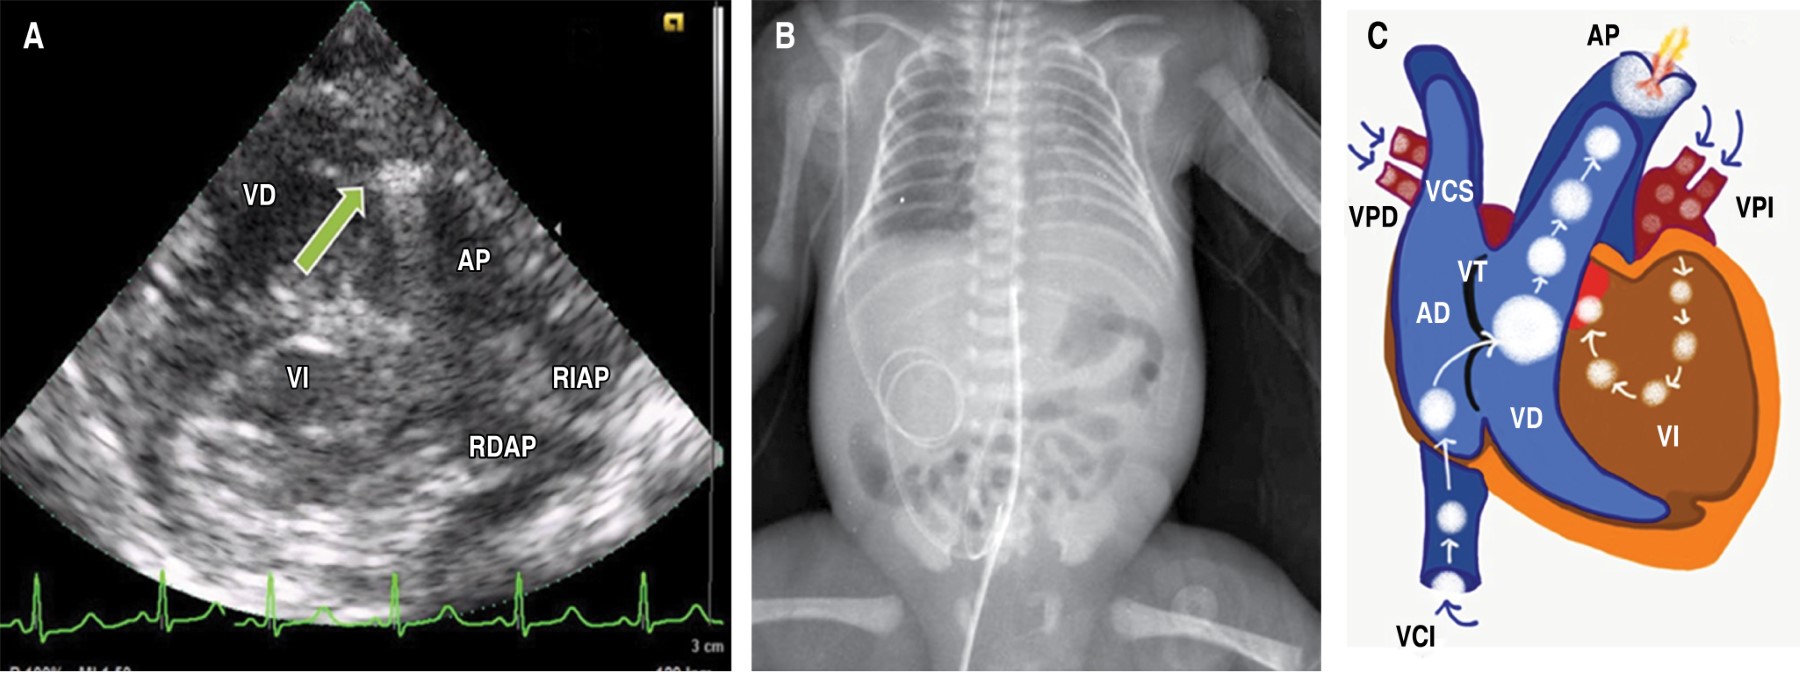

Tras recalentamiento y estabilización inicial, a las nueve horas de vida se realizó USG cardiaco en el que se observó circulación de transición, incremento en las resistencias vasculares pulmonares, conducto arterioso permeable (CAP) y foramen oval permeable (FOP) con corto circuito bidireccional, adecuada función biventricular, con gasto cardiaco bajo e hipotensión (33/16 mmHg, siendo el percentil 5 para este paciente 43/21 mmHg). El USG pulmonar mostró adecuado deslizamiento pleural, líneas B coalescentes que generaban un pulmón blanco con broncograma de colapso (Tabla 1 y Figura 1 A-C). El USG transfontanelar no demostró hemorragia intraventricular. Con base en esos hallazgos, se aumentó el volumen intravascular y se inició adrenalina a dosis baja (0.05 μg/kg/min).

El paciente llegó a la UCIN con un catéter arterial y canalizado en una vía periférica; como parte de los cuidados se procedió a "ajustar" el catéter arterial, y además se colocó un catéter umbilical venoso. Minutos después del procedimiento presentó deterioro hemodinámico súbito, insuficiencia respiratoria hipoxémica (FiO2 100%) e incremento de lactato (de 5 a 17 mmol/L), por lo que a las 12 horas de vida se realiza nueva evaluación por USG cardiaco, observando disfunción biventricular grave, presencia de imagen hiperecogénica con sombra acústica en "cola de cometa" en el tracto de salida del ventrículo derecho (TSVD), lo cual generaba obstrucción (Figura 2 A); predominio del cortocircuito de derecha a izquierda a través del CAP de 2.6 mm sin encontrar datos de tamponade. En el USG pulmonar se descartó neumotórax y derrame pleural (Tabla 1 y Figura 1 D-F).

Nuestro caso presentó deterioro súbito de la función cardiaca, lo cual seguramente estuvo relacionado a EA que ocurrió posterior o durante la colocación de un acceso vascular, pero estando con ventilación asistida con presiones altas. El EA se considera una complicación grave; en la serie más grande, en la época antes del uso de surfactante se reportaron 25 casos con sólo un sobreviviente, proponiendo que las dos principales vías de entrada son la rotura de alveolos que genera paso de aire a los capilares y el uso de catéteres umbilicales.11 La presentación clínica más frecuente es el colapso hemodinámico repentino o datos de hipertensión arterial pulmonar grave, manifestándose como insuficiencia respiratoria hipoxémica. En el presente caso no se detectó neumotórax en el ultrasonido, ya que había deslizamiento pleural y líneas B (Figura 1 F) y en la placa de tórax sin datos de fuga aérea (Figura 2 B), por lo cual la entrada de aire parece corresponder a la colocación de catéter umbilical.

El EA puede afectar el corazón debido a que el aire tiende a migrar al TSVD, que es la parte más superior del corazón cuando se está en posición supina, alojándose cerca de la válvula pulmonar (Figura 2 C), causando diversos grados de obstrucción (lo cual se ha descrito como cerradura de aire, o air lock). En casos graves puede presentarse como una atresia pulmonar funcional (Figura 1 D).12 Esto genera un compromiso súbito, por choque hipovolémico dado al cese del retorno venoso pulmonar al corazón izquierdo, además de hipoxemia grave (en nuestro caso, agravada por la anemia), todo esto lleva a un resultado fatal.13